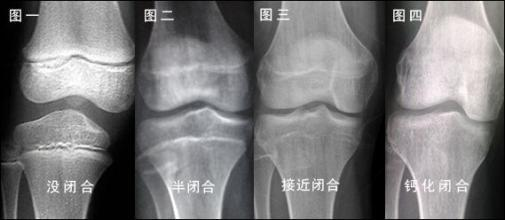

身高增长的本质是长骨(如大腿骨、小腿骨)两端“骨骺”的软骨细胞不断分裂、骨化。这块软骨在X光片上显示为一条透亮的“线”,即骨骺线。当骨骺线完全骨化、闭合,身高增长就基本停止了。

通过拍摄左手腕骨 X 光片,观察骨骺闭合状态是最准确的判断方式。

如果 X 光片显示骨骺线未闭合,说明仍有生长潜力;若已完全闭合,则身高基本定型。即使孩子实际年龄较小,但骨龄超前且接近闭合,生长空间也会受限。

图注:左图,骨骺未闭合;右图:骨骺已闭合